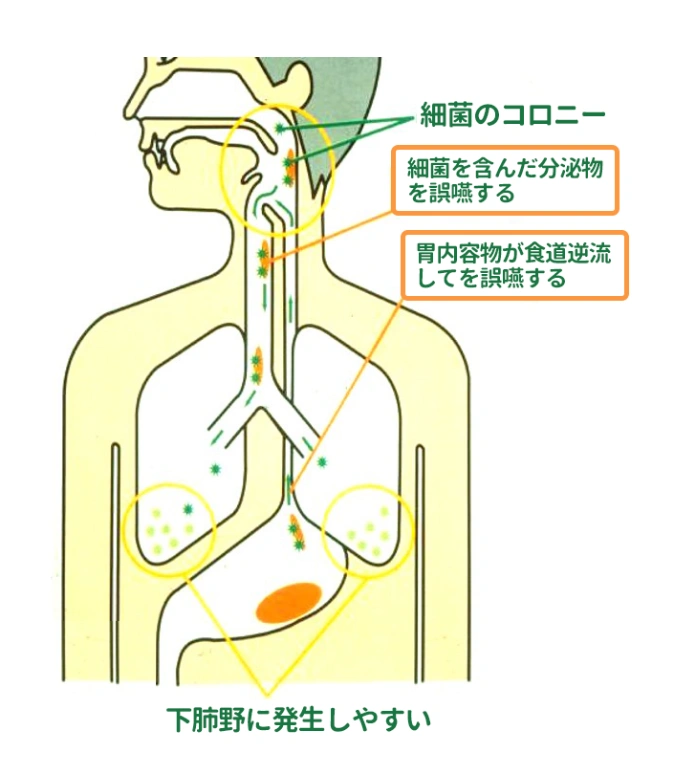

摂食嚥下障害とは、口から食べる機能の障害のことです。私たちは普段意識していませんが、食べ物を目や脳において認識して口まで運び、口の中に入れて噛み、ゴックンと飲み込むことで、食物から液体を摂取しています。これらの動作の1つまたは複数が、何らかの原因で正常に機能しなくなった状態を言います。 健康な成人の方であれば、誤って気管に入った場合も自然反射的に吐き出したり、細菌から身を守る免疫力が十分に備わっているので、大きな問題にはなりませんが、高齢者、 特に寝たきりや身体が不自由な方は、そうした自然反射的な動作が難しいので、細菌が気管に入りやすく、さらに抵抗力や免疫力の低下から、誤嚥性肺炎になりやすいと言われています。

摂食嚥下障害とは、どのような障害か

摂食嚥下障害とは、口から食べる機能の障害のことです。私たちは普段意識していませんが、食べ物を目や脳において認識して口まで運び、口の中に入れて噛み、ゴックンと飲み込むことで、食物から液体を摂取しています。これらの動作の1つまたは複数が、何らかの原因で正常に機能しなくなった状態を言います。 健康な成人の方であれば、誤って気管に入った場合も自然反射的に吐き出したり、細菌から身を守る免疫力が十分に備わっているので、大きな問題にはなりませんが、高齢者、 特に寝たきりや身体が不自由な方は、そうした自然反射的な動作が難しいので、細菌が気管に入りやすく、さらに抵抗力や免疫力の低下から、誤嚥性肺炎になりやすいと言われています。

2.誤嚥性肺炎

摂食嚥下障害とは、口から食べる機能の障害のことです。私たちは普段意識していませんが、食べ物を目や脳において認識して口まで運び、口の中に入れて噛み、ゴックンと飲み込むことで、食物から液体を摂取しています。これらの動作の1つまたは複数が、何らかの原因で正常に機能しなくなった状態を言います。 健康な成人の方であれば、誤って気管に入った場合も自然反射的に吐き出したり、細菌から身を守る免疫力が十分に備わっているので、大きな問題にはなりませんが、高齢者、 特に寝たきりや身体が不自由な方は、そうした自然反射的な動作が難しいので、細菌が気管に入りやすく、さらに抵抗力や免疫力の低下から、誤嚥性肺炎になりやすいと言われています。